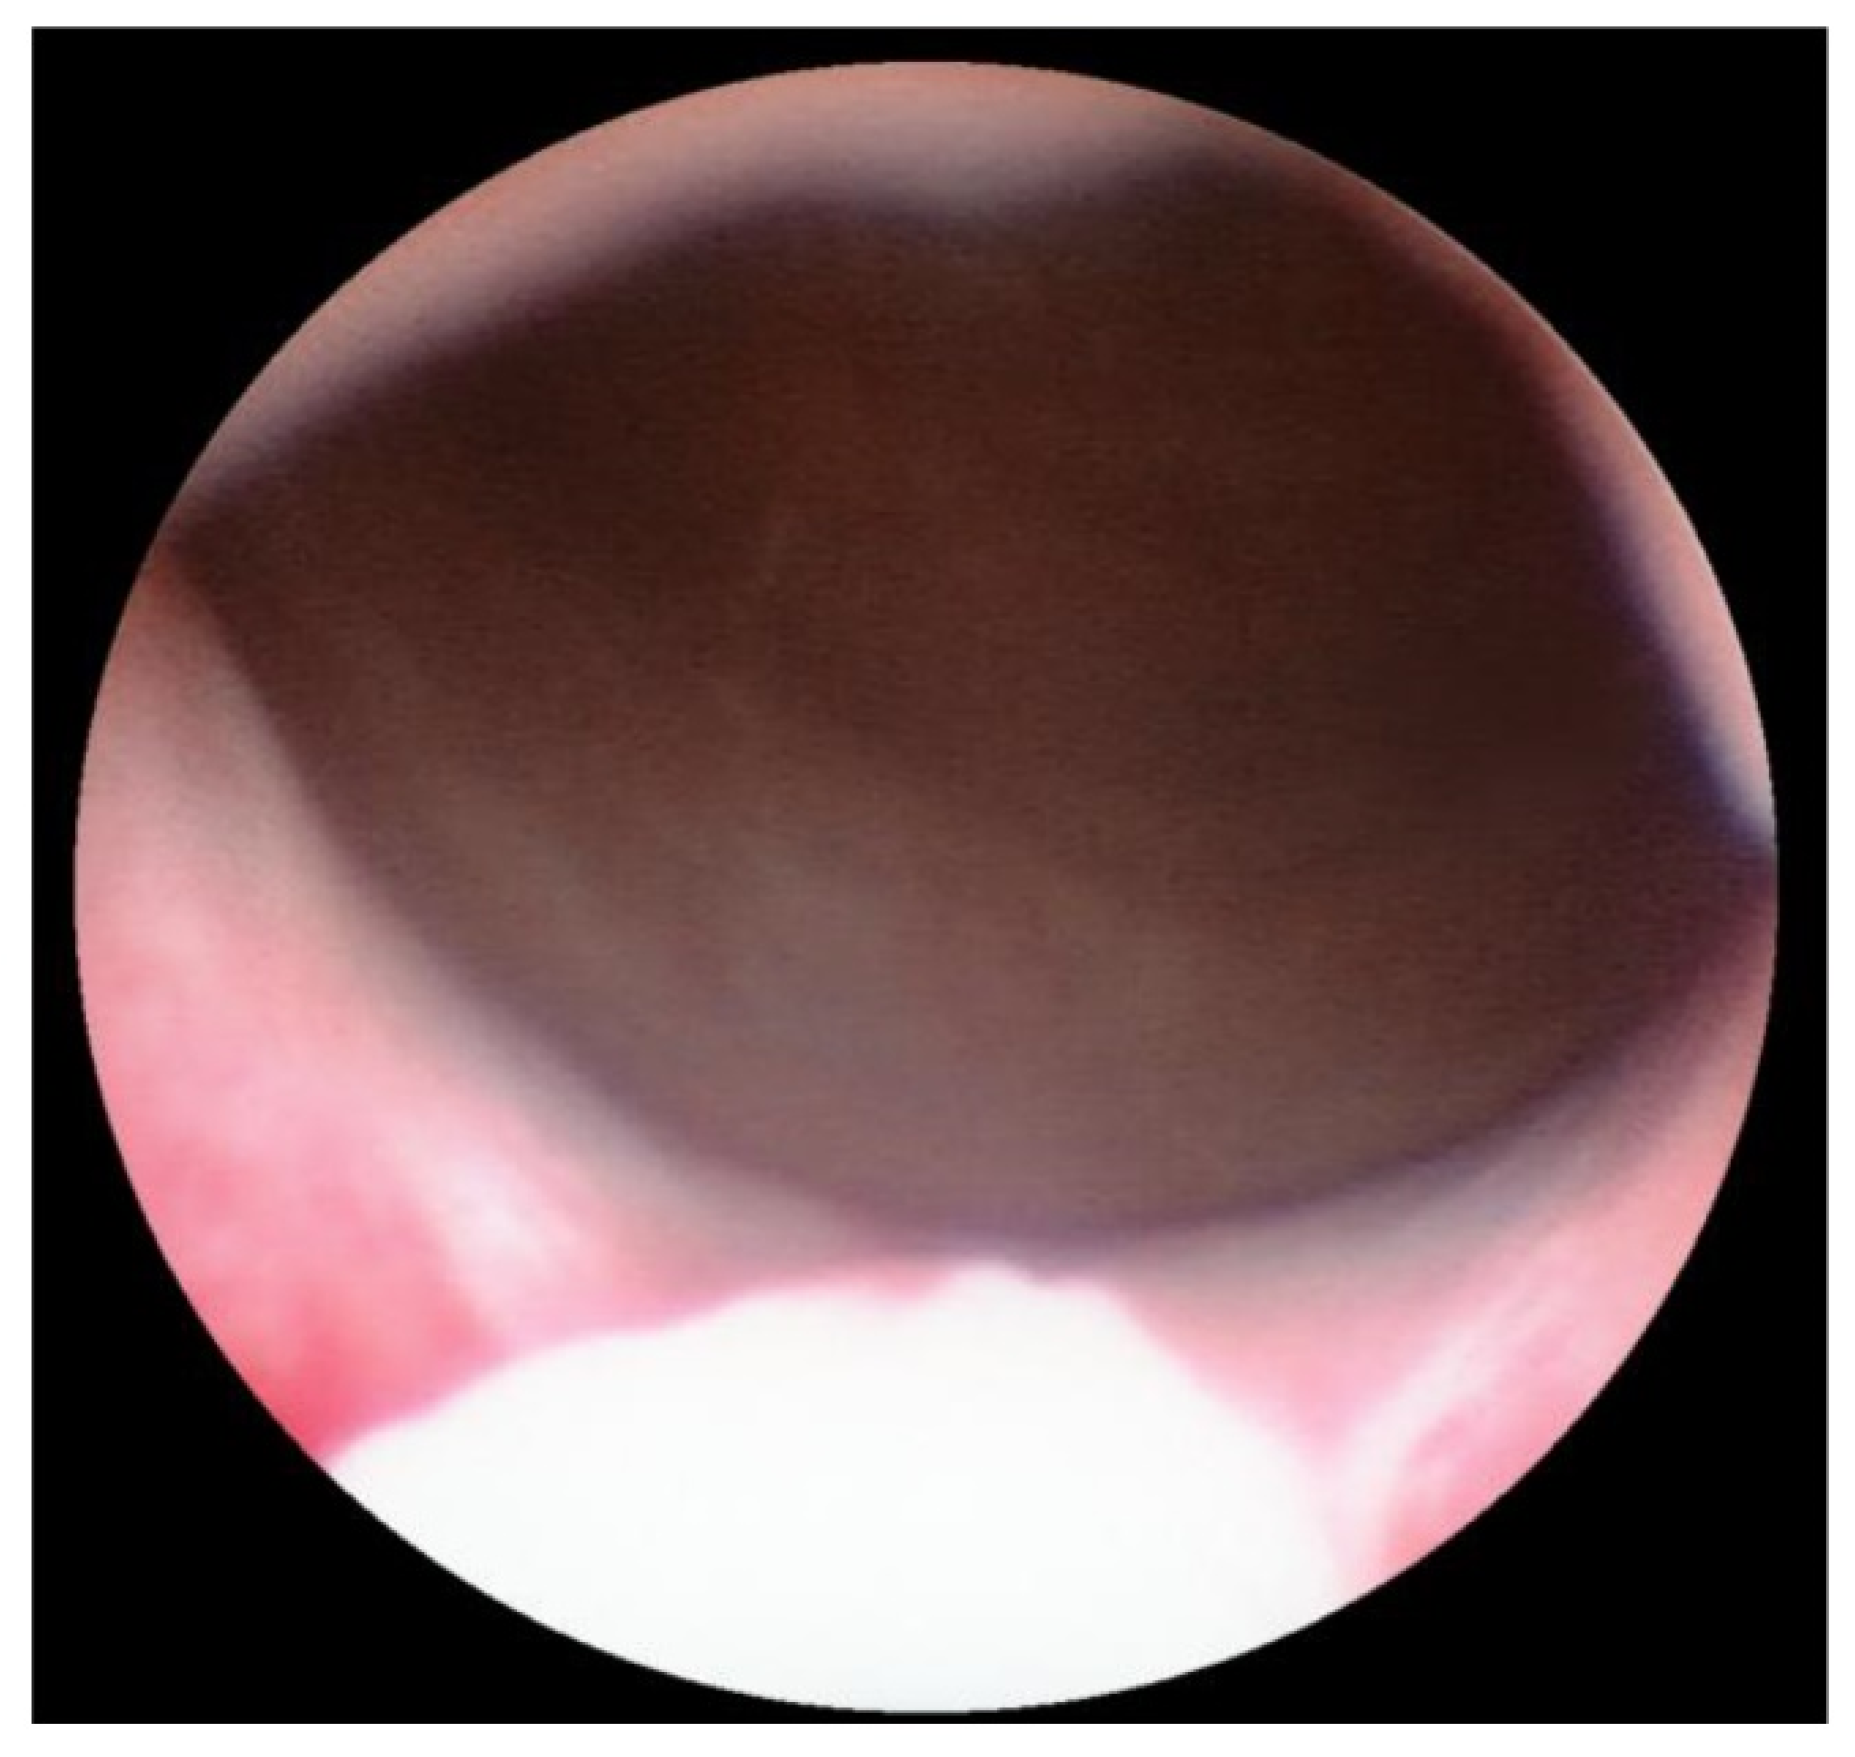

Transurethral cystoscopy displayed a wide open bladder neck at the beginning of the procedure (Figure 5). Under guidance by antegrade suprapubic endoscopy, transurethral retrograde bladder neck injection was performed at the 3 o’clock and 9 o’clock positions (Figure 6). Subsequently, bladder neck injection at the 6 o’clock and 12 o’clock positions was performed through antegrade percutaneous suprapubic endoscopy. Direct antegrade and retrograde visualization confirmed effectiveness of the luminal occlusion (Figure 7). As a (positive) consequence of effective injection, visibility of the optimal location for injection was compromised with increasing volume of the bulking agent. The combined injection technique is helpful to reduce this limitation as much as possible.

Figure 7.

Retrograde cystoscopy confirming effectiveness of luminal occlusion (before injection: see Figure 5).